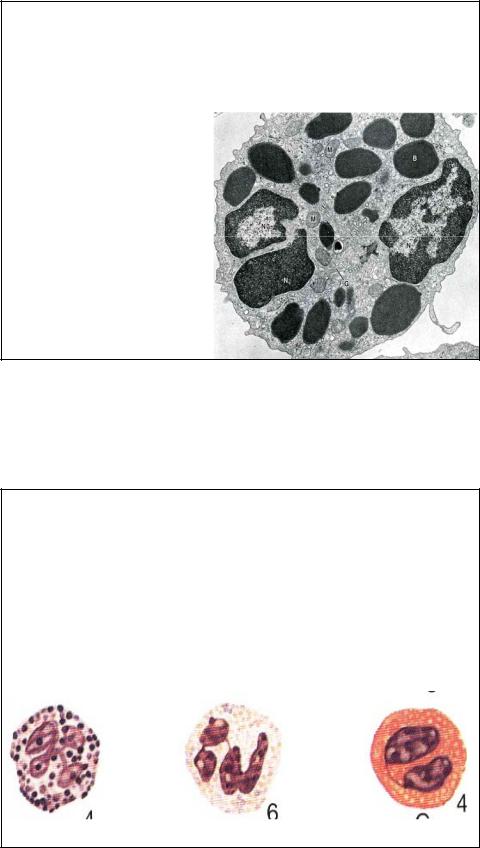

Базофил в мазке крови, x 1325.

Базофилы самые малочисленные из лейкоцитов, диаметр у них 8- 10 мкм. Их цитоплазма заполнена темными крупными базофильными специфическими гранулами (головка стрелки), которые, вдавливаясь в плазмалемму, придают клетке угольчатую форму. Специфические гранулы замаскировывают не только азурофильные клетки, но и само ядро.

39

Специфические гранулы базофилов (0.5 мкм в диаметре) обладают метахромазией, т.е.окрашиваются в цвет. Отличный от цвета красителя. Это связано с присутствием гепарина. Специфические гранулы базофила не столь многочисленны, как у других лейкоцитов. И имеют неправильную форму. Дегрануляция при воспалительных и аллергических реакциях приводит к изменению свертываемости и сосудистой проницаемости. Базофилы содержат гепарин, гистамин, лейкотриены, серотонин. Лейкотриены – это медленно действующие вещества анафилаксии, образующиеся во время аллергических реакций в присутствии IgE.